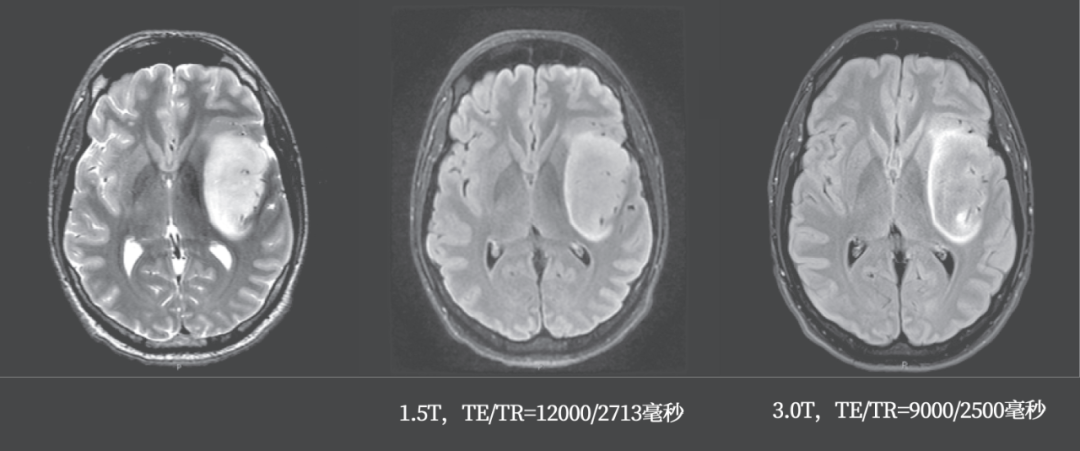

回过头看本病例,肿瘤在 T2WI 呈主体均质高信号,FLAIR 主体呈低信号,周围环形高信号;术后病理为星形细胞瘤 IDH 突变型。

2 例星形细胞瘤 IDH 突变型,均表现为 T2-FLAIR 错配,注意 FLAIR 低信号可以是均匀或不均匀

参数差异可能影响 T2-FLAIR 的呈现